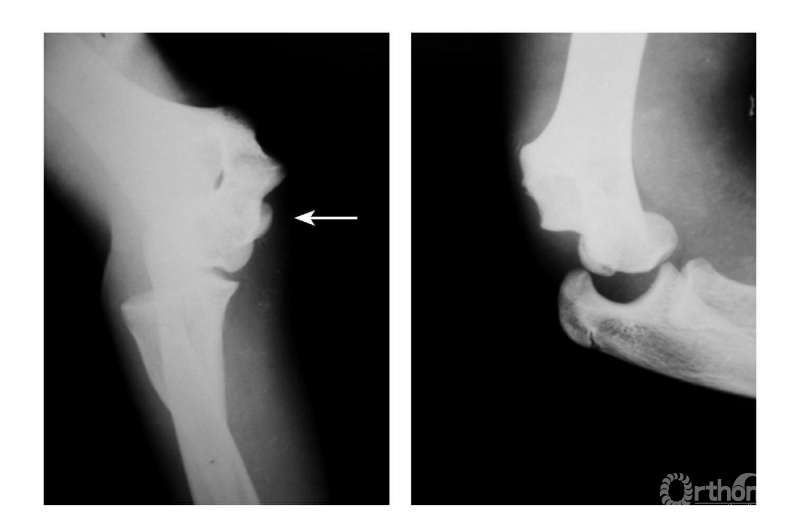

例2:肱骨内上髁Ⅳ度骨折并肘关节旋转性脱位(图10)。

图10